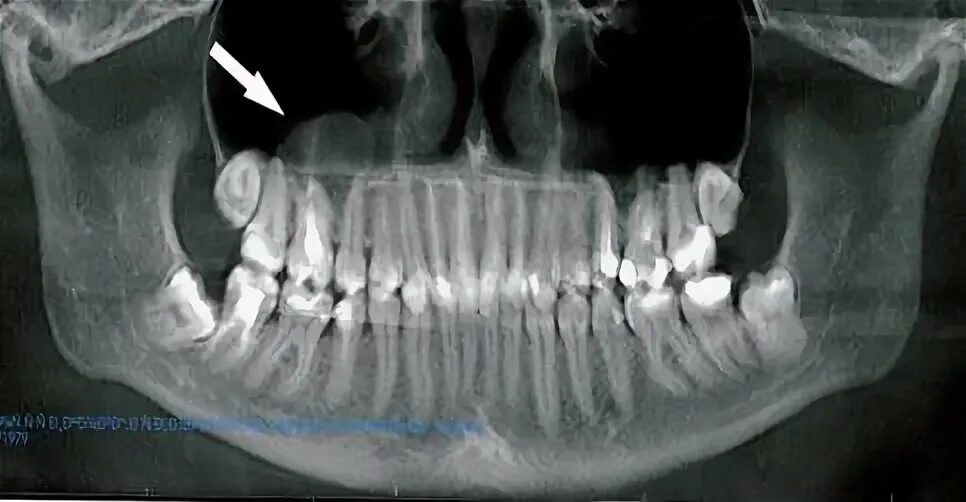

Патологическое содержимое что это